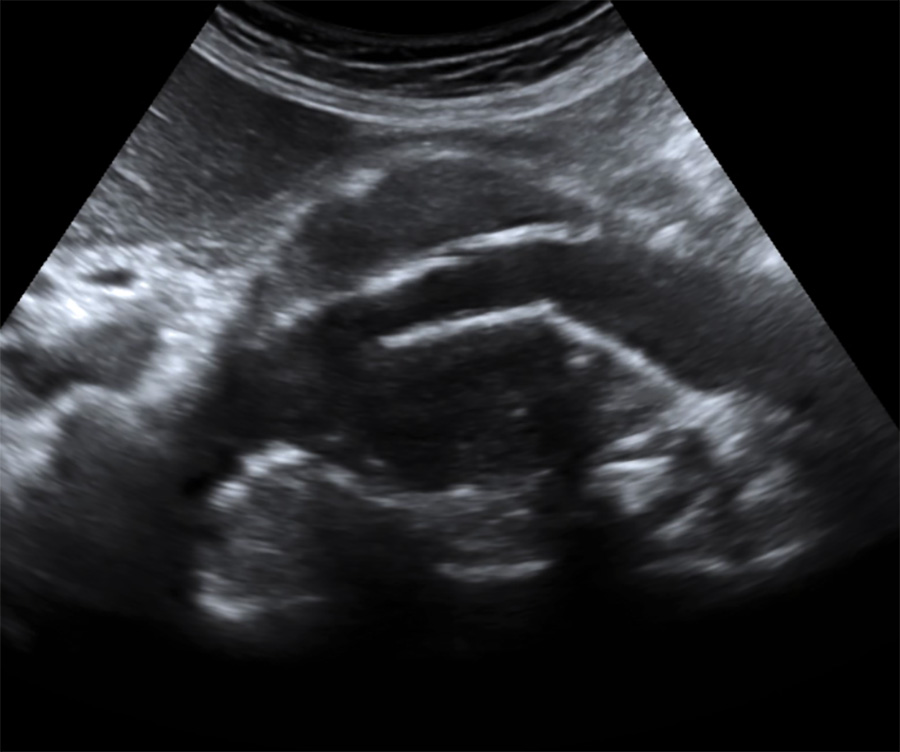

Aspect échographique en coupe longitudinale